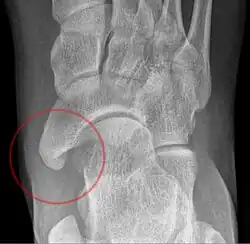

Radiographie du pied montrant un os naviculaire accessoire

Un os naviculaire accessoire est un os accessoire du pied qui se développe parfois anormalement devant la cheville vers l'intérieur du pied. Cet os peut être présent dans environ 2 à 14 % de la population générale et est généralement asymptomatique[1],[2],[3]. Lorsqu'il est symptomatique, une intervention chirurgicale peut être nécessaire.

L'os naviculaire accessoire peut provoquer un étirement continu et une tension sur le tendon postérieur tibial qui peut évoluer vers une douleur chronique invalidante et peut provoquer une rupture du tendon ou une déformation secondaire du pied plat, lorsque cela se produit, cette condition est communément appelée syndrome naviculaire accessoire[4]. D'autres conditions qui imitent étroitement les symptômes d'un os naviculaire accessoire incluent fasciite plantaire, oignons et épine calcanéenne.

Les radiographies sont généralement commandées pour confirmer le diagnostic. S'il y a une douleur ou une inflammation en cours, une IRM ou d'autres tests d'imagerie avancés peuvent être utilisés pour évaluer davantage la condition.

Images radiologiques